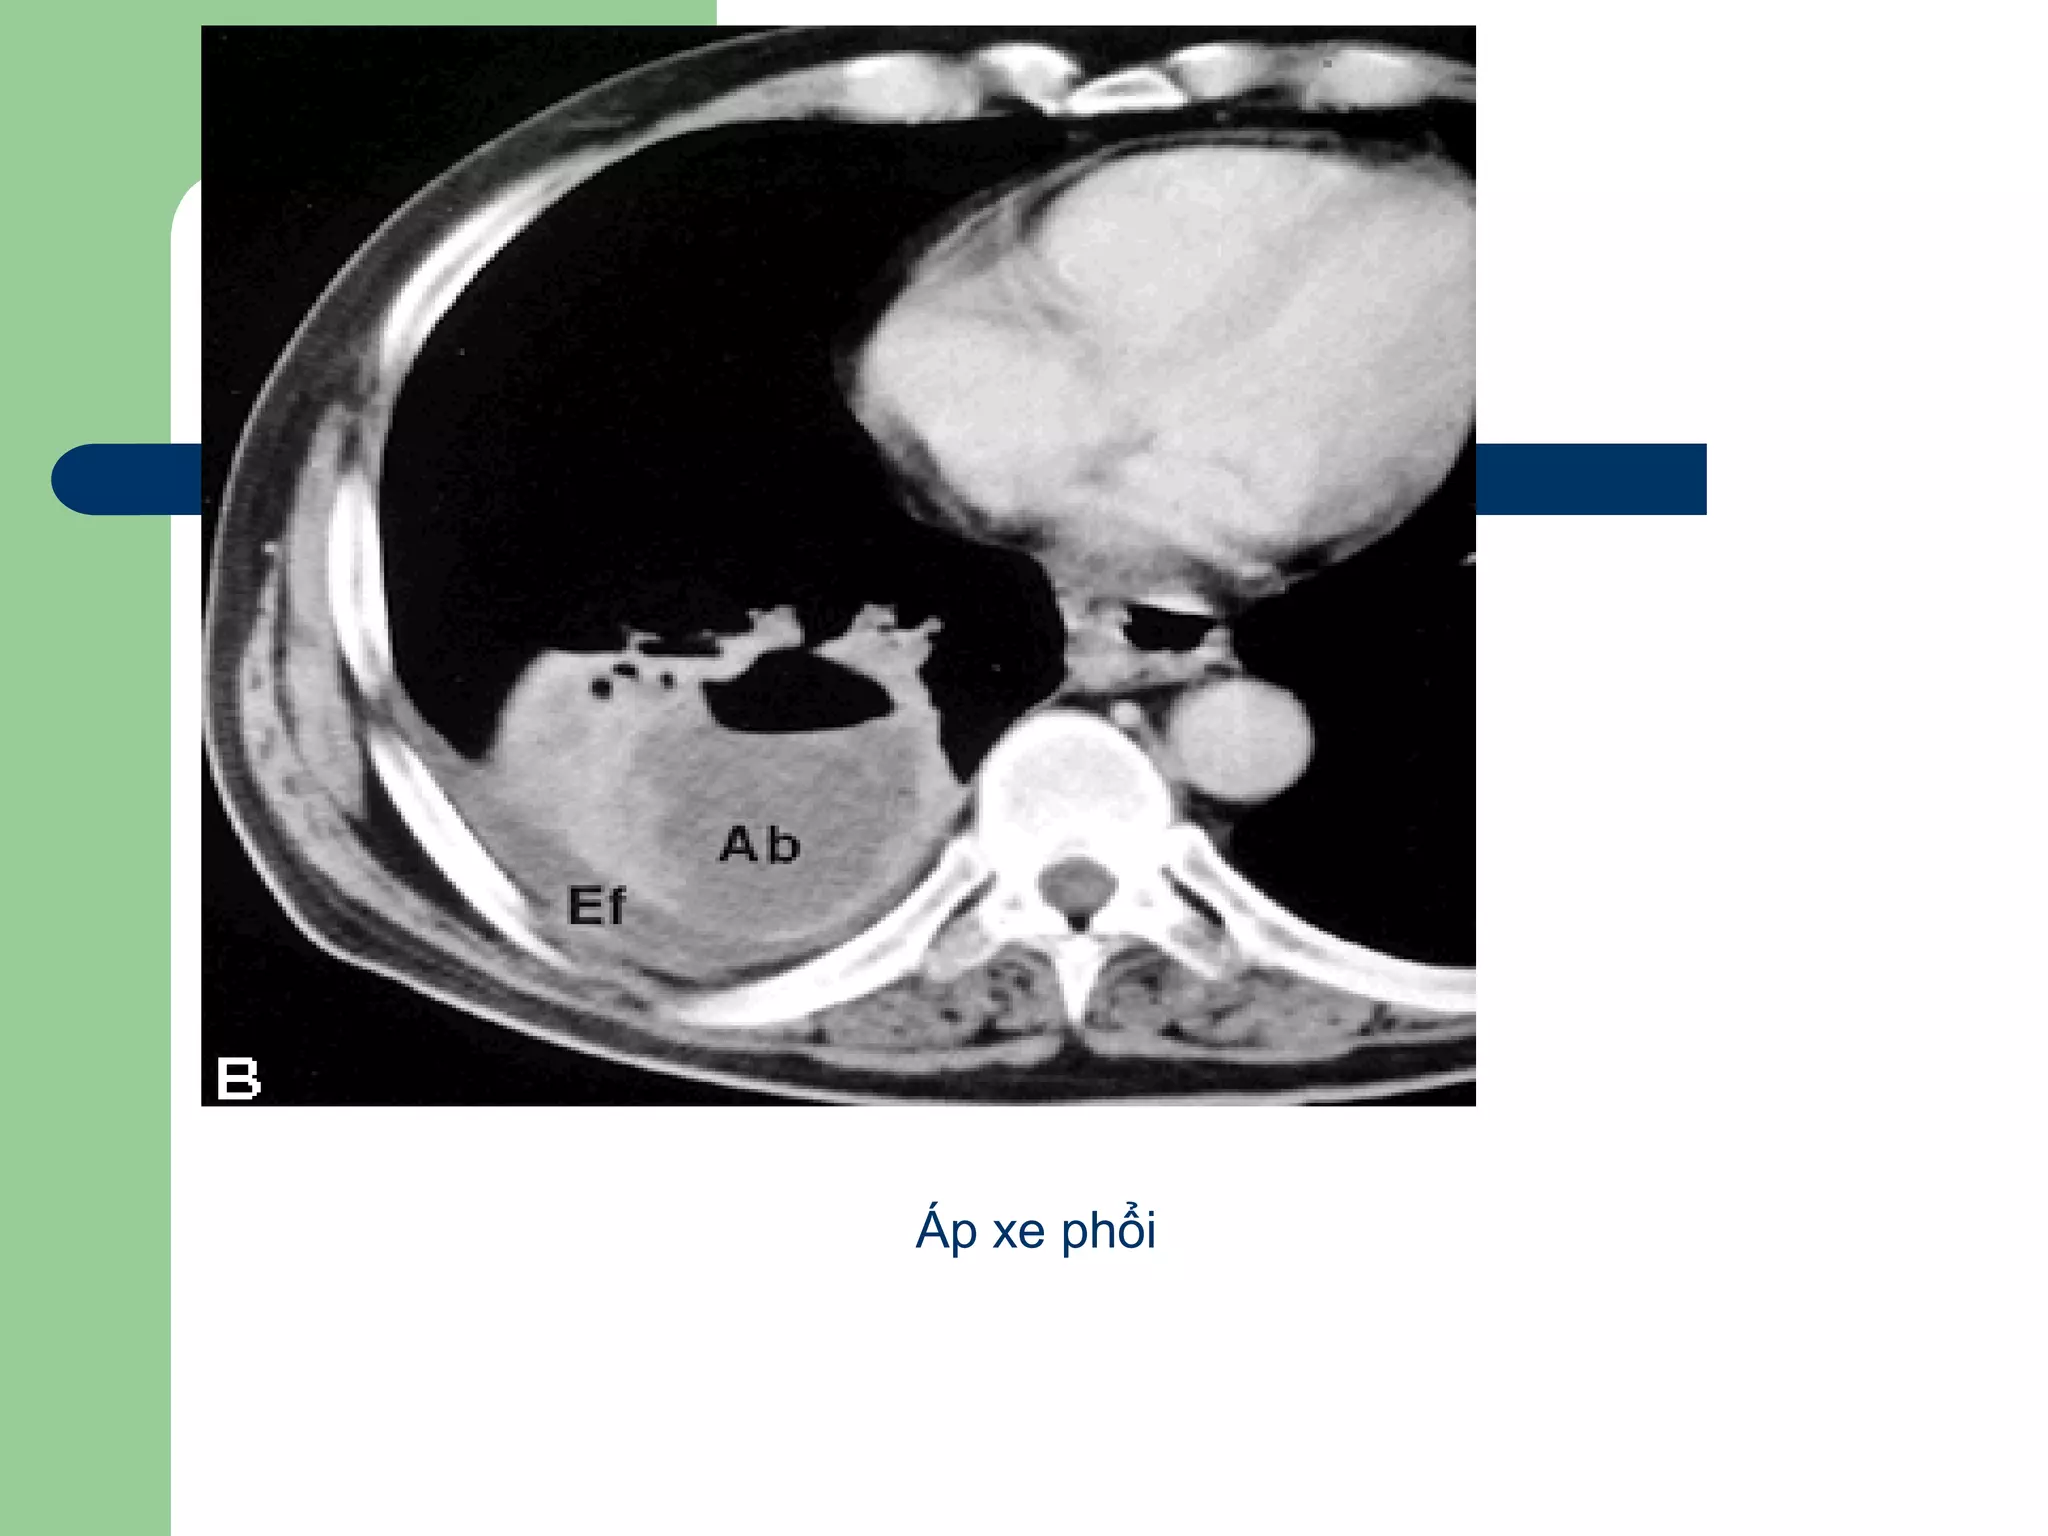

Áp xe phổi

 Do vi khuẩn (tụ cầu, Klebsiella)

 CT: GĐ đầu, vùng giảm đậm độ xung

quanh là vùng đông đặc phổi

Khi ổ áp xe rõ, tăng quang ngoại

biên (thành ổ áp xe), không tăng quang

trung tâm (vùng họai tử), mức khí dịch

nếu thông với phế quản

*CĐPB: u phổi họai tử, tụ mủ màng phổi

Aùp-xe phoåi